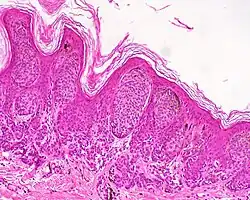

| Type | Characteristics | Photo- graphy |

Histo- pathology |

|---|---|---|---|

| Dysplastic nevus | Usually a compound nevus with cellular and architectural dysplasia. Like typical moles, dysplastic nevi can be flat or raised. While they vary in size, dysplastic nevi are typically larger than normal moles and tend to have irregular borders and irregular coloration. Hence, they resemble melanoma, appear worrisome, and are often removed to clarify the diagnosis. Dysplastic nevi are markers of risk when they are numerous, such as in people with dysplastic nevus syndrome. According to the National Institute of Health (NIH), doctors believe that, when part of a series or syndrome of multiple moles, dysplastic nevi are more likely than ordinary moles to develop into the most virulent type of skin cancer called melanoma.[19] | ![]() In this case, the central portion is a complex papule, and the periphery is macular, irregular, indistinct and slightly pink. |

Characteristic rete ridge bridging, shouldering, and lamellar fibrosis. H&E stain.

|